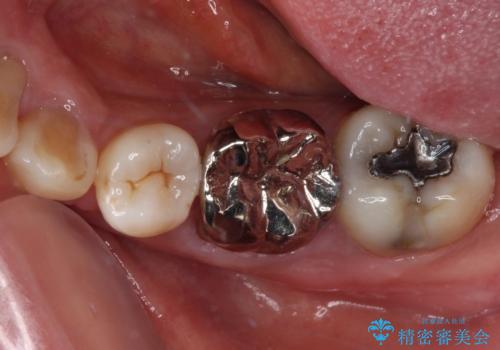

- 矯正治療後に、下顎奥歯の銀歯をすべてゴールドにすることを希望された患者様です。

セラミッククラウンやセラミックインレーによる補綴治療も提案しましたが、お友達にゴールドを自慢したいとのことで、ゴールドクラウンとゴールドインレーにて処置することとしました。